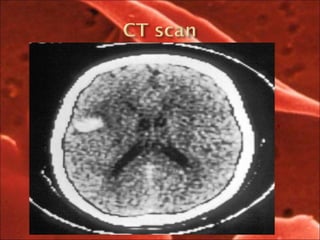

 CNS-25% patient have TIA, strokes, cerebral hemorrhage,rpls reversible

post leuco encephalopathy syndrme.